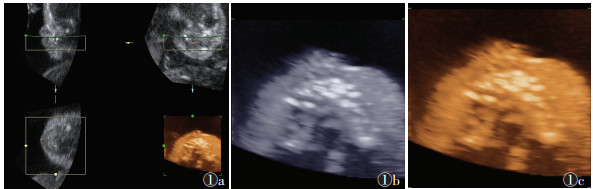

![]() |

| 图 1 31岁,26周胎儿正常腭部三维重建图像 图 1a 重建出的腭部三维图像,左上图为竖直矢状面,右上图为冠状面,左下图为轴面,右下图为腭部重建后所显示的渲染图像 图 1b,1c 为图 1a右下图放大的图像,可调节颜色及亮度增加对比度 |